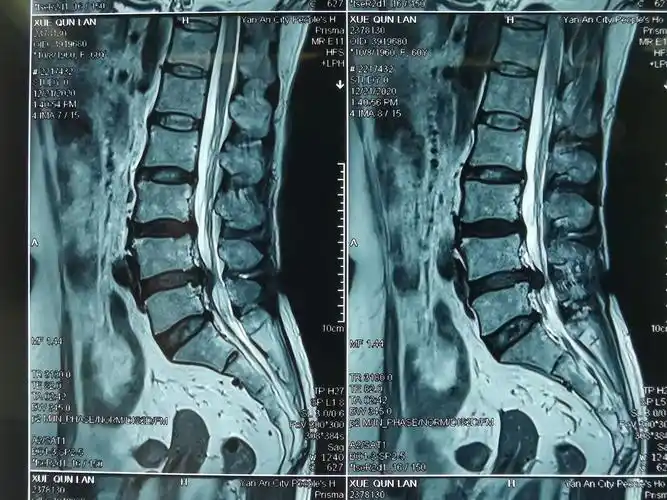

腰椎片子

腰椎核磁共振片